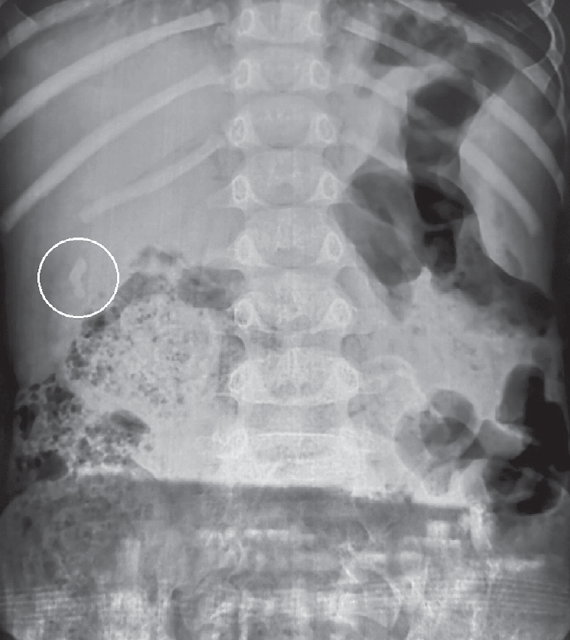

Возраст пациентов был от 2 до 17 лет. В 70,4 % случаев заболевание отмечено у девочек, соответственно у мальчиков — 29,6 %. У 7,8 % пациентов заболевание возникло на фоне гемолитической анемии. Около трети пациентов предъявляли жалобы на умеренно выраженный болевой синдром или чувство тяжести в верхней половине живота. У 15 % детей клинические симптомы возникали на фоне погрешностей в диете. При этом клинические и биохимические показатели анализов крови и мочи, в том числе печеночного профиля, были в пределах нормы. Вышеуказанные симптомы послужили показанием к проведению ультразвукового исследования (УЗИ). У пациентов с бессимптомным течением ЖКБ УЗИ было назначено по другому поводу. При проведении УЗИ у всех пациентов в желчном пузыре обнаруживали гиперэхогенные образования (рис. 1), смещаемые при изменении положения тела (конкременты).

Рис. 1. Ультразвуковая картина конкремента в желчном пузыре

Fig. 1. Ultrasonic pattern of concretion in the gallbladder